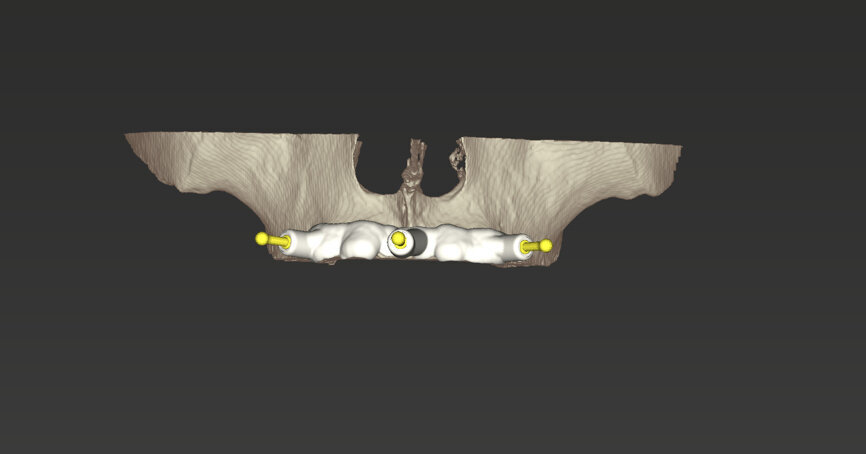

An intra-oral scan was taken to record the patient’s current oral situation, and the resulting STL file and the DSD fil (2D smile design image) were used to create the future prosthetic design with software for the laboratory (Figs. 3–6). The 3D radiographic DICOM data and the prosthetic design project STL file were superimposed in coDiagnostiX (Figs. 7–9) The fixation pin guide, bone reduction guide, surgical guide and bite registration guide were designed with coDiagnostiX (Figs. 10–13) and produced using 3D printing technology.

To design the prosthesis digitally, we first selected the screw-retained abutment (SRA) angle and gingival height (Fig. 14) and then we created the patient model on which we could connect the BLX implants with the SRAs selected from the Straumann library (Fig. 15). The implant placement guide was on the model, leveraging the high stability that we could gain from palatal support (Figs. 16 & 17). After printing the model, the BL  implant analogues were positioned using the template for navigation. The digital planning using coDiagnostiX (Version 9.14) allowed the dental technician to identify all the necessary parameters related to implant position (Figs. 18–22). Emergence profiles were set-up on the model (Fig. 23). The model was scanned using scan bodies, and a CAD/CAM temporary restoration was designed and milled in a PMMA-based restorative material (Figs. 24–29).